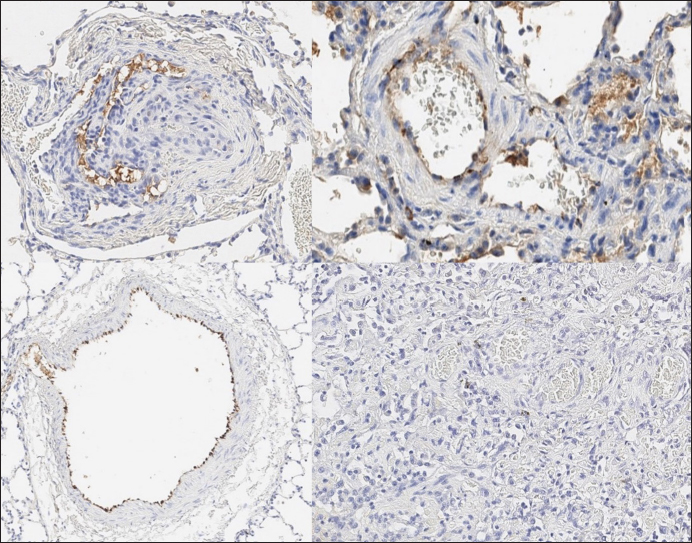

Immunohistochemical labeling with anti-CD31 antibody and anti-factor von Willebrand antibody showed wide dispersion between the groups. In the RHF group, we found a weak-to-absent reaction for the CD31 marker in most of the fibrotic fields, restricted to endothelial cells. Additionally, we discovered an intensive reaction to von Willebrand factor in most arterioles and in vessels with plexiform morphology. In sPCH animals, we observed significant expression of CD31 marker covering most of the fields and actively present in alveolar septae with numerous capillaries. However, the representation of von Willebrand factor was almost absent (Figs. 6 and 7).

Fig. 6. RHF group. Immunohistochemistry. Left top right top, left bottom—factor von Willebrand active expression on endothelial surface in pulmonary vessels. Right bottom—absence of reaction on CD31 marker of endothelial cells.